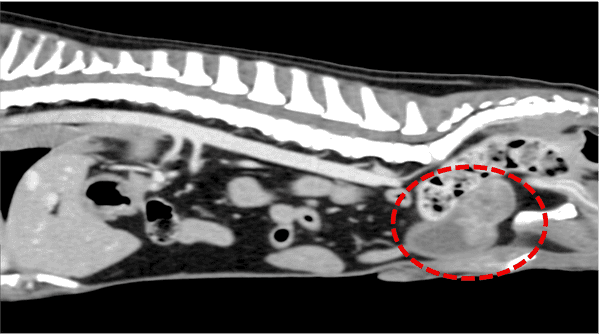

前立腺原発 尿路上皮癌うたがい →外力カテーテル法により得られた尿沈渣をBRAF遺伝子変異検査に外注 →BRAF遺伝子変異陽性 第14病日 CT撮影実施 (図2) →リンパ節、肺、その他臓器への転移所見なし